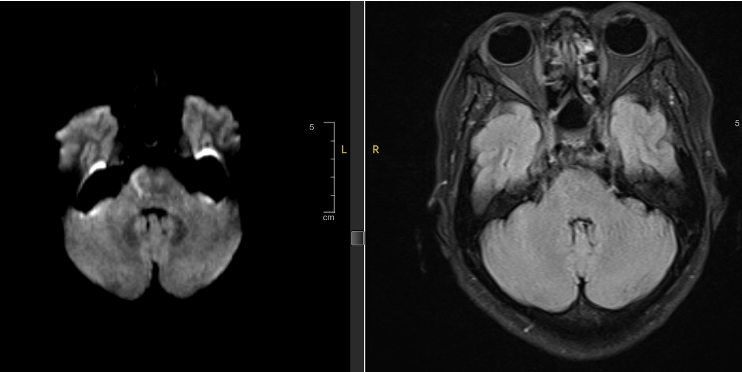

Hình ảnh Mismatch trên xung DWI và FLAIR của bệnh nhân P.T.N

Từ kết quả chụp MRI của 2 bệnh nhân, cho thấy có sự bất tương xứng (có Mismatch) giữa xung DWI và FLAIR (Hình 1 và Hình 3). Do đó trong 2 trường hợp này, sau khi hội chẩn bệnh nhân vẫn có chỉ định điều trị bằng thuốc tiêu huyết khối (rTPA) nhằm tái thông lại mạch máu đang tắc nghẽn.